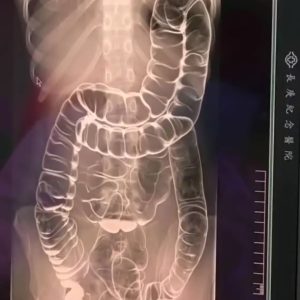

Everything you need to know about chronic constipation: A hidden threat to your digestive health

Chronic constipation can have serious negative health effects if ignored. Our digestive system breaks down the food we consume, allowing the body to absorb essential nutrients. During digestion,...